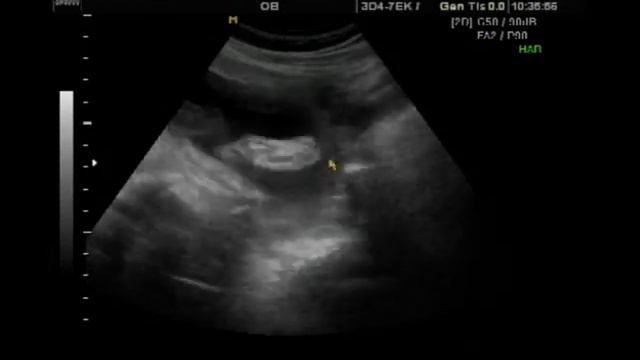

исутствовала на узи

Присутствовала на узи 118 фотографий

Диамед 24